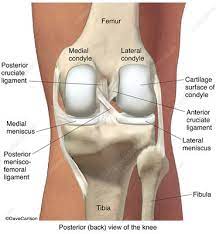

Lateral aspect of medial femoral condyle most common location. The motions of the condyles include rocking, gliding and rotating. In the knee, chondromalacia is usually related to injury, overuse of the knee, and poorly aligned muscles and bones around the knee joint. Methods sixteen knees with a small medial femoral. When ocd affects the knee, the most common location is within the lateral aspect of the medial femoral condyle. Medial condyle of femur from wikipedia, the free encyclopedia the medial condyle is one of the two projections on the lower extremity of femur, the other being the lateral condyle. The femoral condyle allograft has been used for resurfacing cartilage defects with mature hyaline cartilage for several decades, with very high success rates. The medial femoral condyle is supplied by a plexus of vessels from the descending genicular artery and the medial superior genicular artery.

They are called the medial and the lateral femoral condyle, respectively. An imbalance of the muscles around the knee (some muscles are weaker than others.) overuse (repeated bending or twisting) of the knee joint, especially during sports. However, two of the patients had one or more fractures missed when they first presented. The medial femoral condyles are the bony protrusions on the inside edge of the bottom of the femur bone in each thigh. Osteochondritis dissecans (ocd) is an acquired, reversible, idiopathic lesion. Osteonecrosis of the medial femoral condyle presents as a sudden onset of pain on the medial side of the knee. This is associated with a positive bone scan and, frequently, a radiolucent lesion in the subchondral zone. Methods sixteen knees with a small medial femoral. The medial condyle is larger than the lateral (outer) condyle due to more weight bearing caused by the centre of mass being medial to the knee. Medial condyle of femur from wikipedia, the free encyclopedia the medial condyle is one of the two projections on the lower extremity of femur, the other being the lateral condyle. Root tear (radial tear) of the medial meniscus mild or moderate knee arthritis Osteonecrosis of the medial femoral condyle can be treated in a variety of ways depending on the stage of the disease. Of the six patients who had suffered an isolated fracture of their medial condyle, four of the patients had their fractures diagnosed on the first visit.

The medial femoral condyle is supplied by a plexus of vessels from the descending genicular artery and the medial superior genicular artery. Medial condyle of femur from wikipedia, the free encyclopedia the medial condyle is one of the two projections on the lower extremity of femur, the other being the lateral condyle. This is associated with a positive bone scan and, frequently, a radiolucent lesion in the subchondral zone. Osteonecrosis of the medial femoral condyle presents as a sudden onset of pain on the medial side of the knee. Three bones meet within the knee joint: Cartilage can be focally damaged, producing a pot hole in the joint surface, when the knee ligaments are injured. Versatility of the medial femoral condyle flap for extremity reconstruction and identification of risk factors for nonunion, delayed time to union, and complications. Juvenile ocd lesions have a better healing prognosis than adults. The medial condyle is named for its location on the inside of the knee, closer to the midline of the body, while the lateral condyle is found on the outside of the knee, away from the midline of the body. One presumed mechanism of injury is a stieda fracture (avulsion injury of the medial collateral ligament at the medial femoral condyle). Methods sixteen knees with a small medial femoral. The motions of the condyles include rocking, gliding and rotating. Based on the patient's antalgic gait and radiographic findings, the patient was instructed on the proper use of crutches and referred to an orthopaedic surgeon for appropriate management.